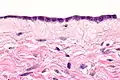

Serous cystadenomas are diagnosed by histomorphologic examination, by pathologists. Grossly, they are, usually, small unilocular cysts that contain clear, straw-coloured fluid. However, they may sometimes be multilocular. Microscopically, the cyst lining consists of a simple epithelium, whose cells may be either:[3]

- be columnar and tall and contain cilia, resembling normal tubal epithelium

- be cuboidal and have no cilia, resembling ovarian surface epithelium